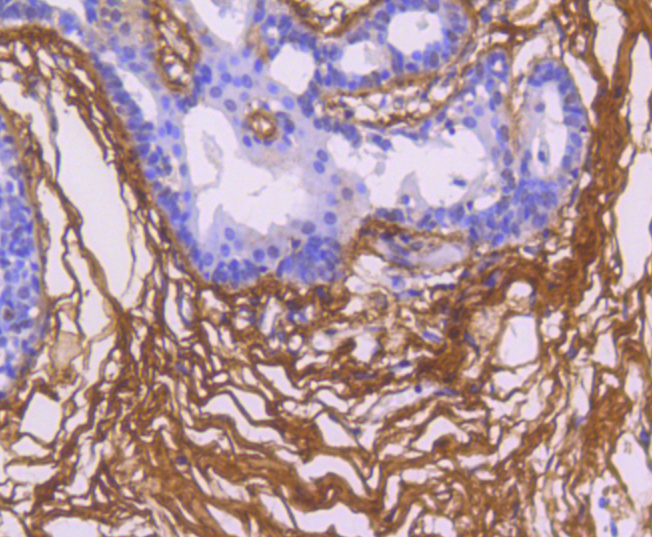

图片:

Immunohistochemical analysis of paraffin-embedded human breast carcinoma tissue using anti-Fibronectin antibody. Counter stained with hematoxylin.

,

Immunohistochemical analysis of paraffin-embedded human gastric carcinoma tissue using anti-Fibronectin antibody. Counter stained with hematoxylin.